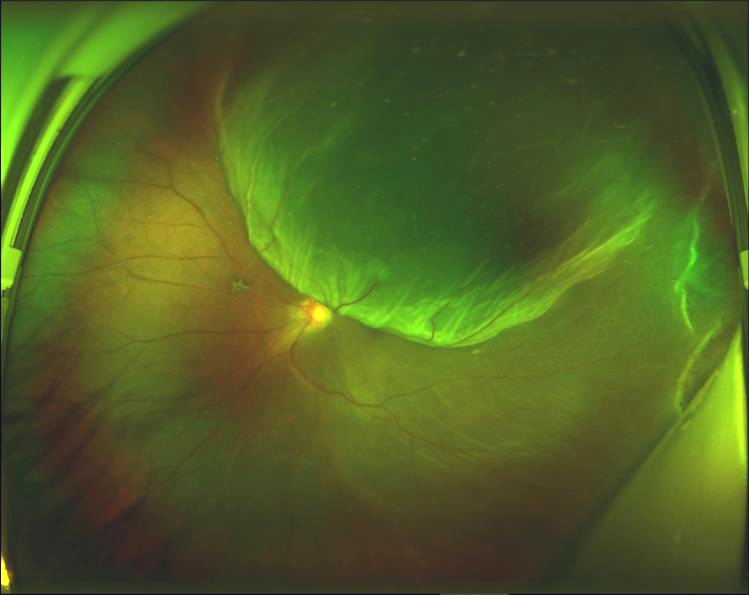

多見于中年或老年人,多數(shù)有近視,雙眼可先后發(fā)病。發(fā)病的誘因有視網(wǎng)膜周邊部的格子狀和囊樣變性,玻璃體液化變性和視網(wǎng)膜粘連,這些誘因又和年齡、遺傳、外傷等因素有關(guān),玻璃體對(duì)視網(wǎng)膜的牽引,在發(fā)病機(jī)理上更顯得重要。近年來,年輕的發(fā)病者也不斷增加,患者中甚至出現(xiàn)了不滿十歲的小學(xué)生。發(fā)病原因多數(shù)為外傷或用眼過度。

• 中心視力下降:后極部的視網(wǎng)膜脫落,視力急劇下降。周邊部初脫時(shí),對(duì)中心視力無影響或影響甚小。同樣在高危病人有視力下降時(shí)應(yīng)詳細(xì)檢查眼底。

• 視物變形:當(dāng)周邊部視網(wǎng)膜脫落波及后極或后極部發(fā)生淺脫落時(shí),除中心視力下降外,尚有視物變形。

• 視野缺損:視網(wǎng)膜脫落時(shí),部分敏感患者可發(fā)覺視野缺損。但僅下方視野缺損有早期診斷價(jià)值。